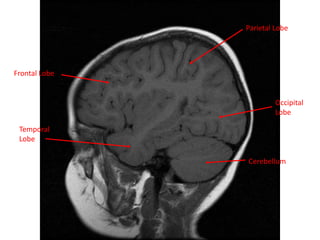

MRI BRAIN :SAGITTAL SECTIONS

White Matter

Cerebellum

Grey Matter

Frontal Lobe

Parietal Lobe

Temporal Lobe

Lateral Sulcus Occipital Lobe